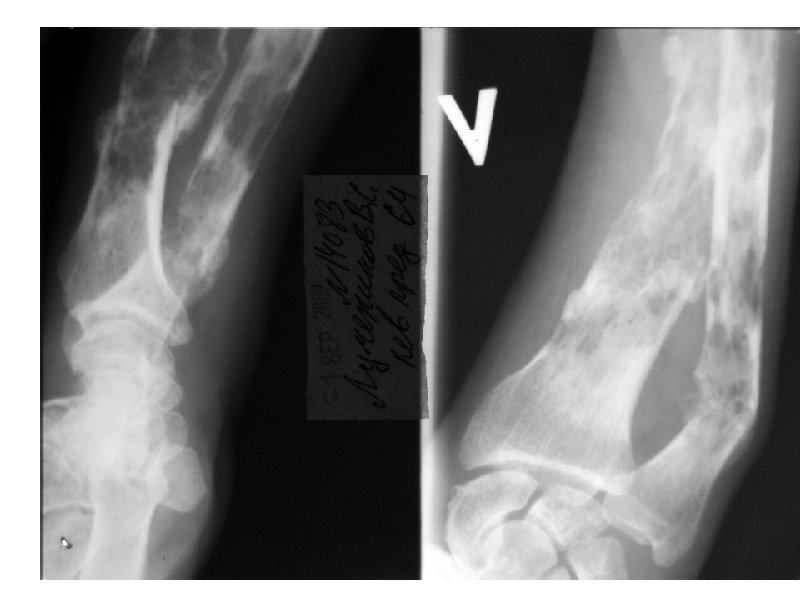

Клинические проявления ММ • Множественные остеолитические очаги Поражение костей повреждения плоских костей и эпифизов трубчатых костей • Диффузный остеопороз (остеопения) • Костные переломы • Уменьшение роста (вертебральный коллапс) Эффекты, ассоциированные с остеодеструкцией Внекостные плазмацитомы • Болевой синдром у 20 -40% Гиперкальциемия ( утомляемость, жажда, тошнота, запоры, повреждение почек, полиурия, сонливость, судороги, кома) • Гиперкальцийурия • Вовлечение мягких тканей преимущественно в области головы/шеи, очаги в печени, почках,

А- рентгенограмма, В- мультидетекторная КТ (МДКТ), Смагнитнорезонансная томография (МРТ)

А-ренгенограмма, В-МДКТ